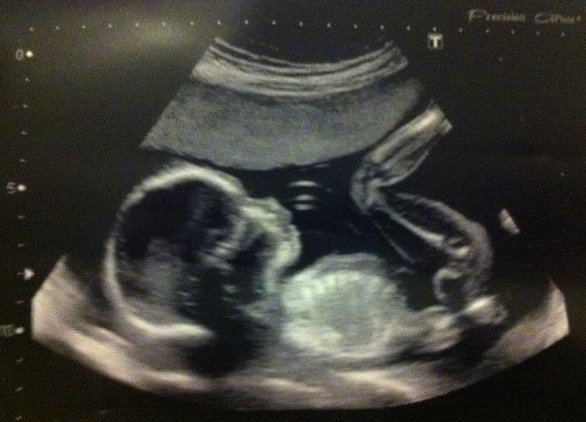

20 Week Scan